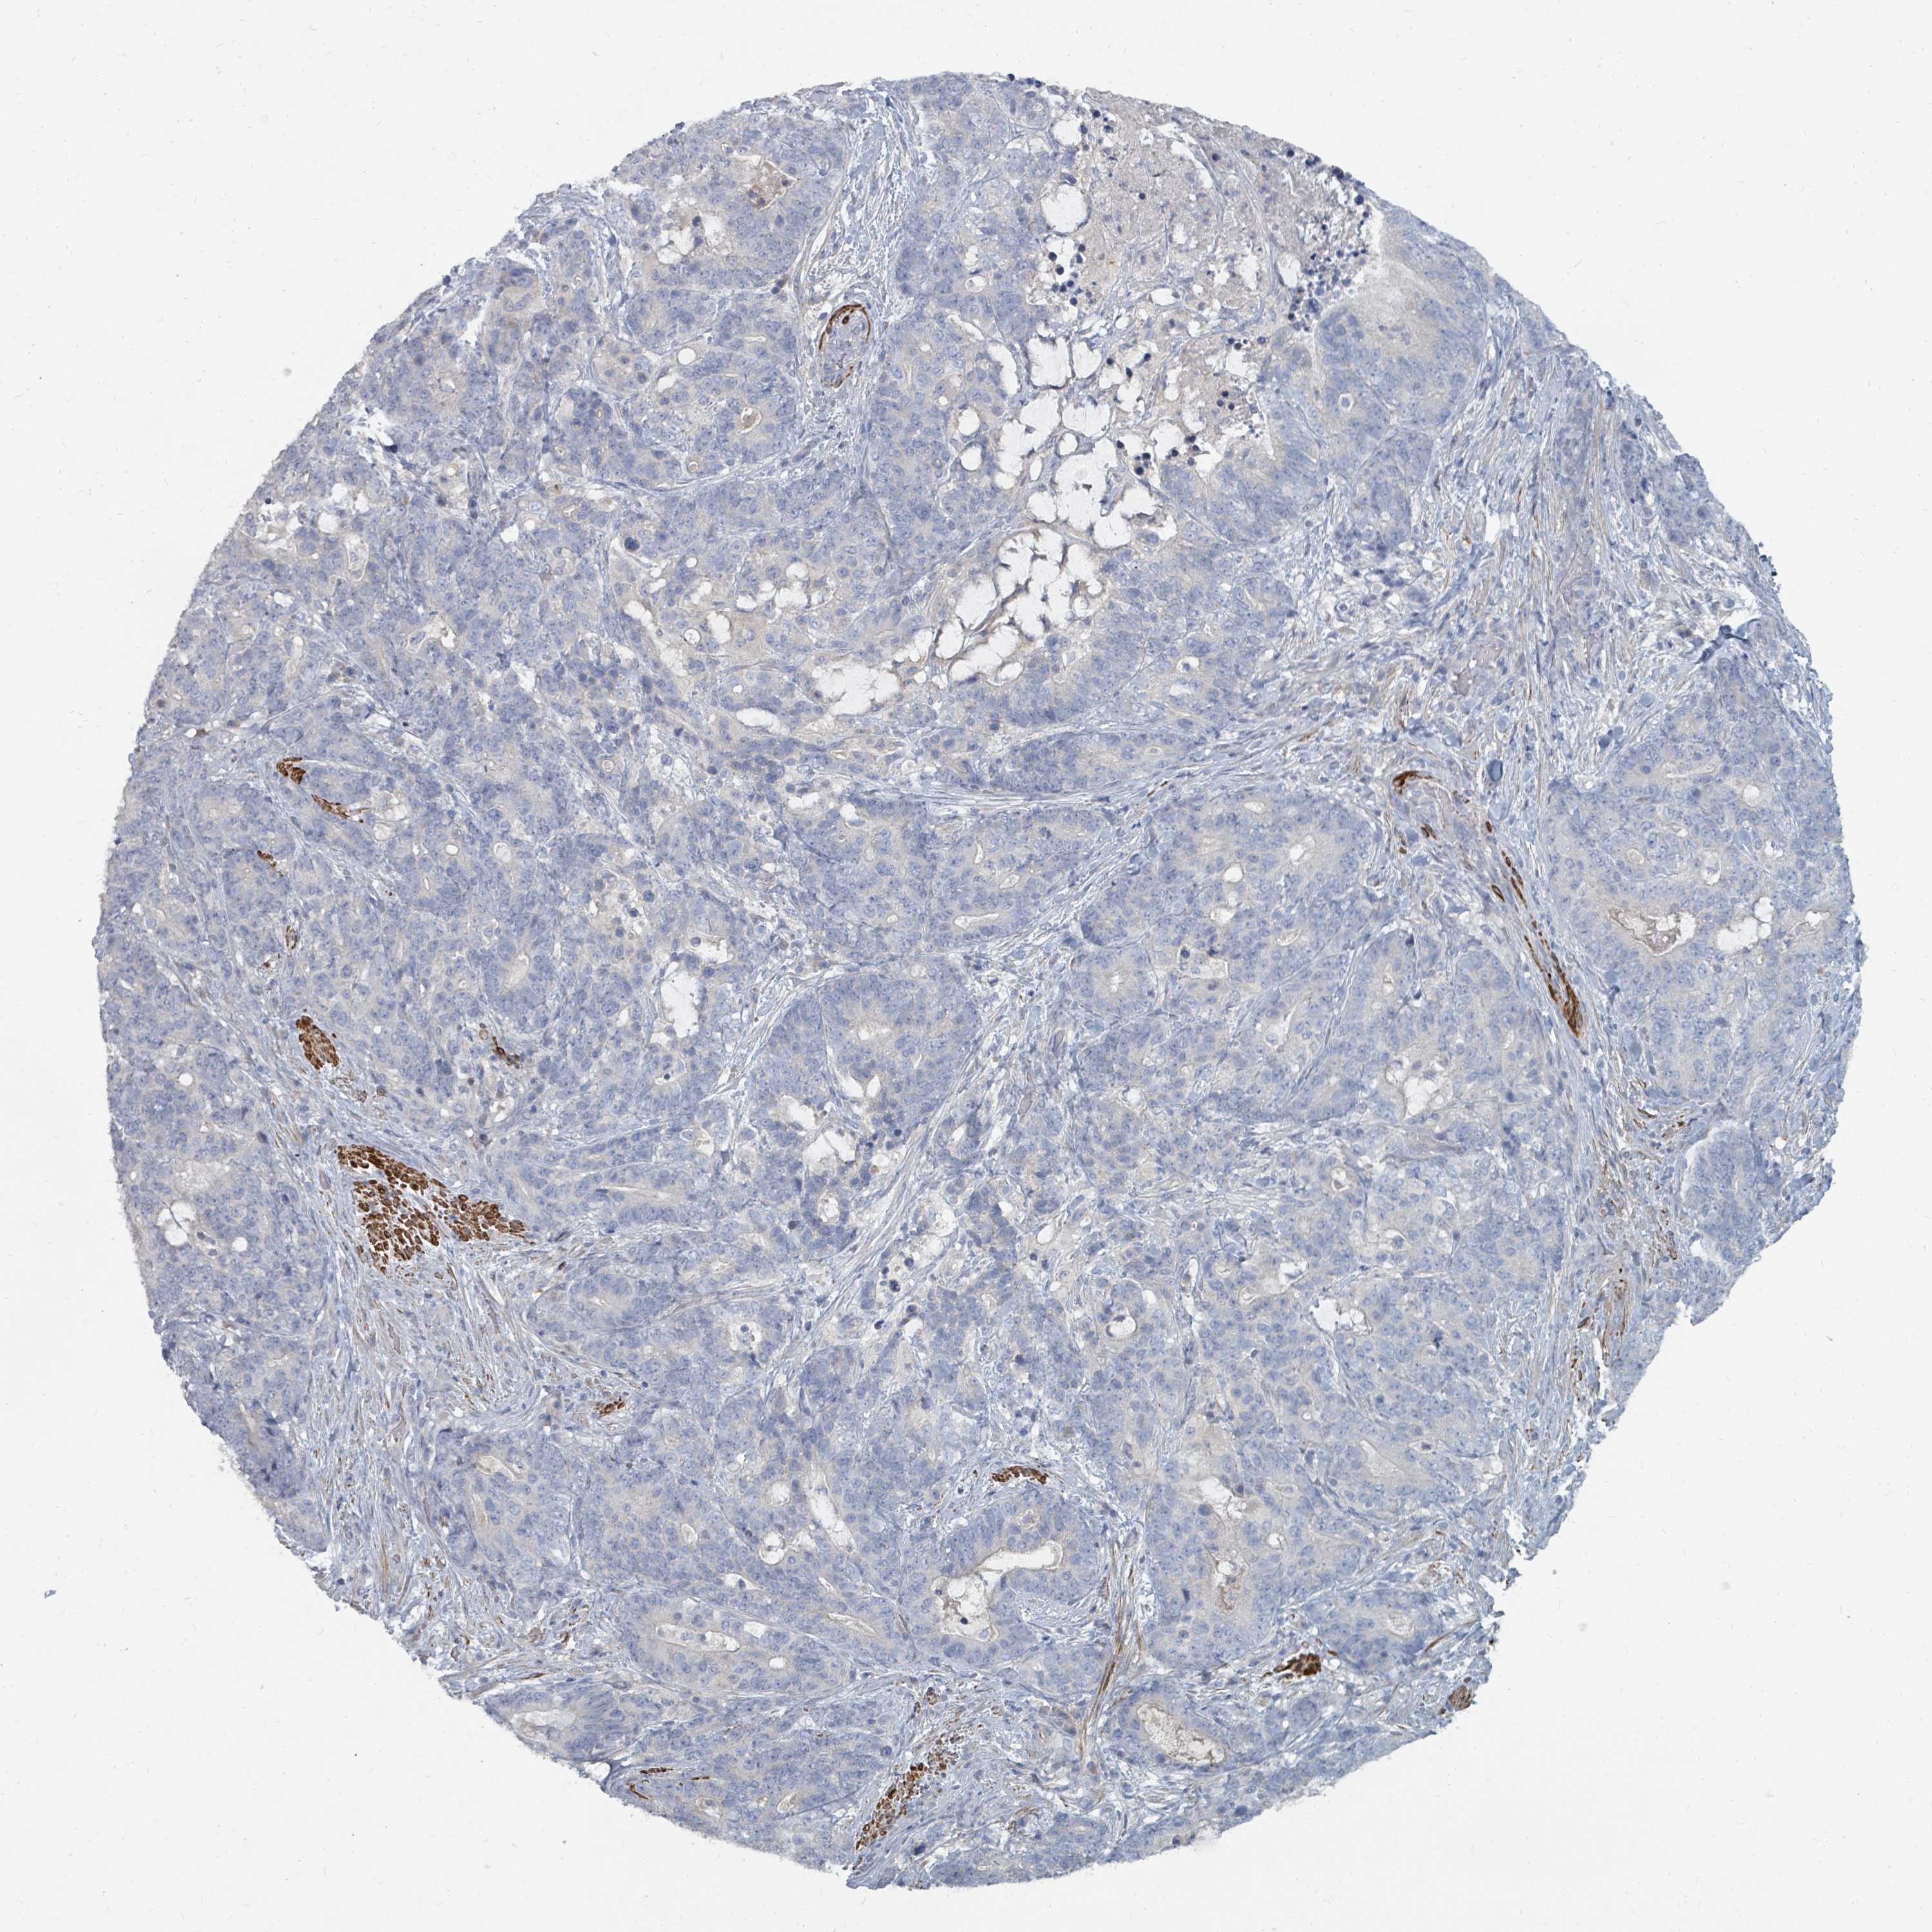

STOMACH CANCER - Protein expressioni

A mouse-over function shows sample information and annotation data. Click on an image to view it in a full screen mode. Samples can be filtered based on level of antibody staining by selecting one or several of the following categories: high, medium, low and not detected. The assay and annotation is described here.

Note that samples used for immunohistochemistry by the Human Protein Atlas do not correspond to samples in the TCGA dataset.

Antibody stainingi

Antibody staining in the annotated cell types in the current human tissue is reported as not detected, low, medium, or high, based on conventional immunohistochemistry profiling in selected tissues. This score is based on the combination of the staining intensity and fraction of stained cells.

Each image is clickable and will lead to virtual microscopy that enables deeper exploration of all samples and also displays staining intensity scores, fraction scores and subcellular localization as well as patient and tissue information for each sample.

Antibody HPA043049

Staining

High

Medium

Low

Not detected

Intensity

Strong

Moderate

Weak

Negative

Quantity

>75%

75%-25%

<25%

None

Location

Nuclear

Cytoplasmic/membranous

Cytoplasmic/membranous,nuclear

Adenocarcinoma, NOS